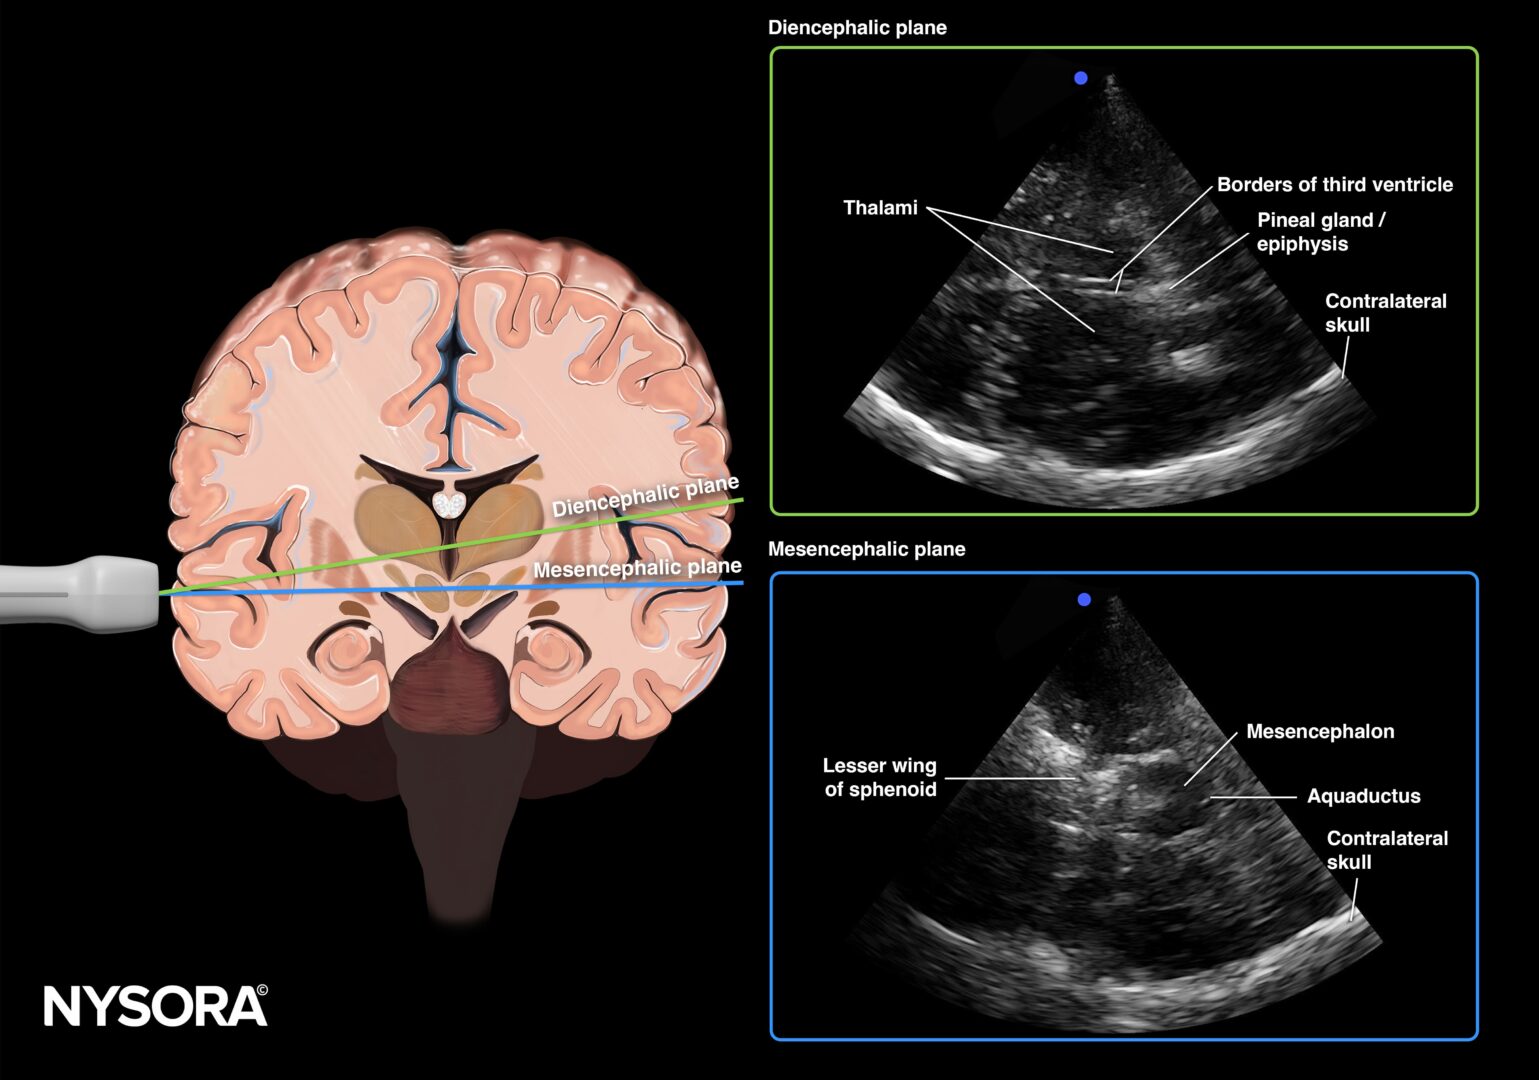

A comprehensive learning tool for anesthesiologists, emergency, and critical care physicians, offering structured modules across eight organ systems, including lung, cardiac, abdominal, renal, and vascular. It integrates step-by-step protocols with high-quality ultrasound images, videos, animations, and NYSORA’s Reverse Ultrasound Anatomy to simplify interpretation of normal and pathological findings.

Detailed anatomical illustrations and ultrasound images.

Reverse Ultrasound Anatomy illustrations for intuitive sonoanatomy recognition.

NYSORA’s proprietary Reverse Ultrasound Anatomy simplifies the understanding of sonoanatomy.

Reverse Ultrasound Anatomy illustrations make sonoanatomy easier to understand and apply.

• Transcranial Doppler